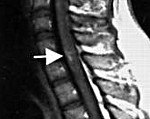

Нетравматичных методов диагностики миелита (разумеется, если нужно установить точную причину, а не предварительный диагноз) нет. Наиболее полную информацию дает люмбальная пункция. При остром процессе назначают КТ или МРТ позвоночника и миелографию.